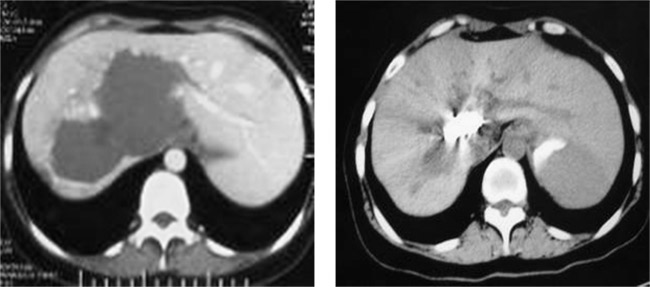

以下是成功病例的CT影像对比:

女,46岁,肝门区巨大海绵状血管瘤,肝动脉栓塞及经皮穿刺平阳霉素碘油乳剂注射,治疗后肿瘤完全消失。